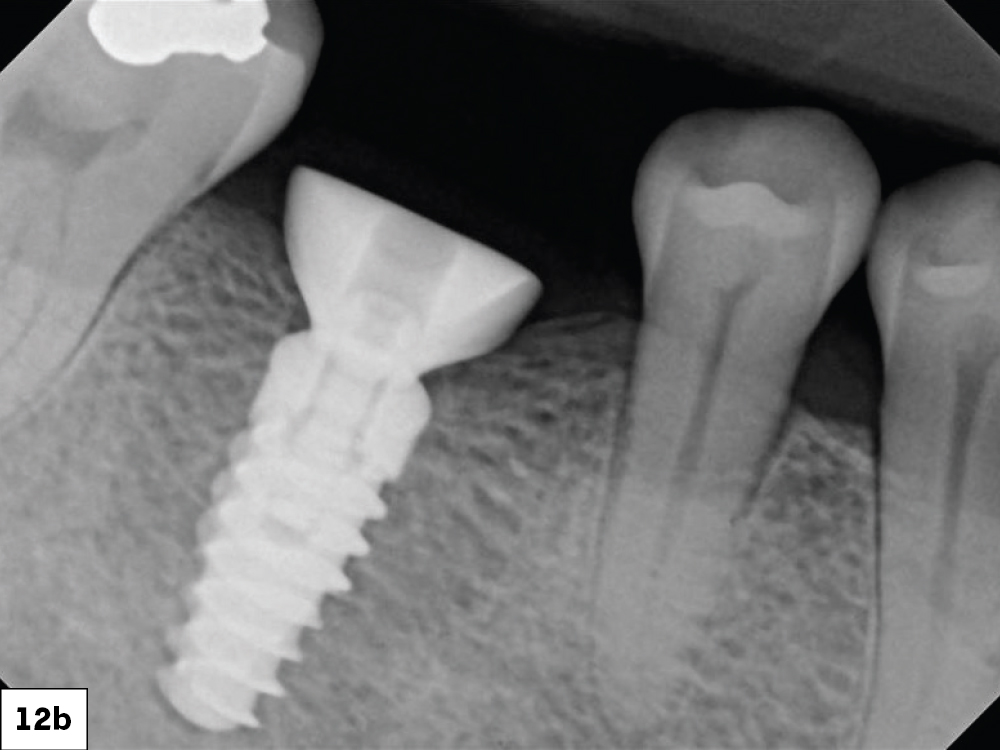

X-Ray of the Fully Inserted Implant Screw

Figures 12a, 12b: Two interrupted sutures were placed using Biotex™ Non-resorbable PTFE Sutures (available through Glidewell Direct), one on the mesial and one on the distal.